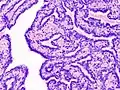

| Histopathology of intraductal papilloma of the breast by excisional biopsy. Immunostaining for p63 protein. | |

Histopathology of intraductal papilloma of the breast by excisional biopsy. Hematoxylin and eosin stain.

Histopathology of intraductal papilloma of the breast by excisional biopsy. Immunostaining for alpha-smooth muscle actin.